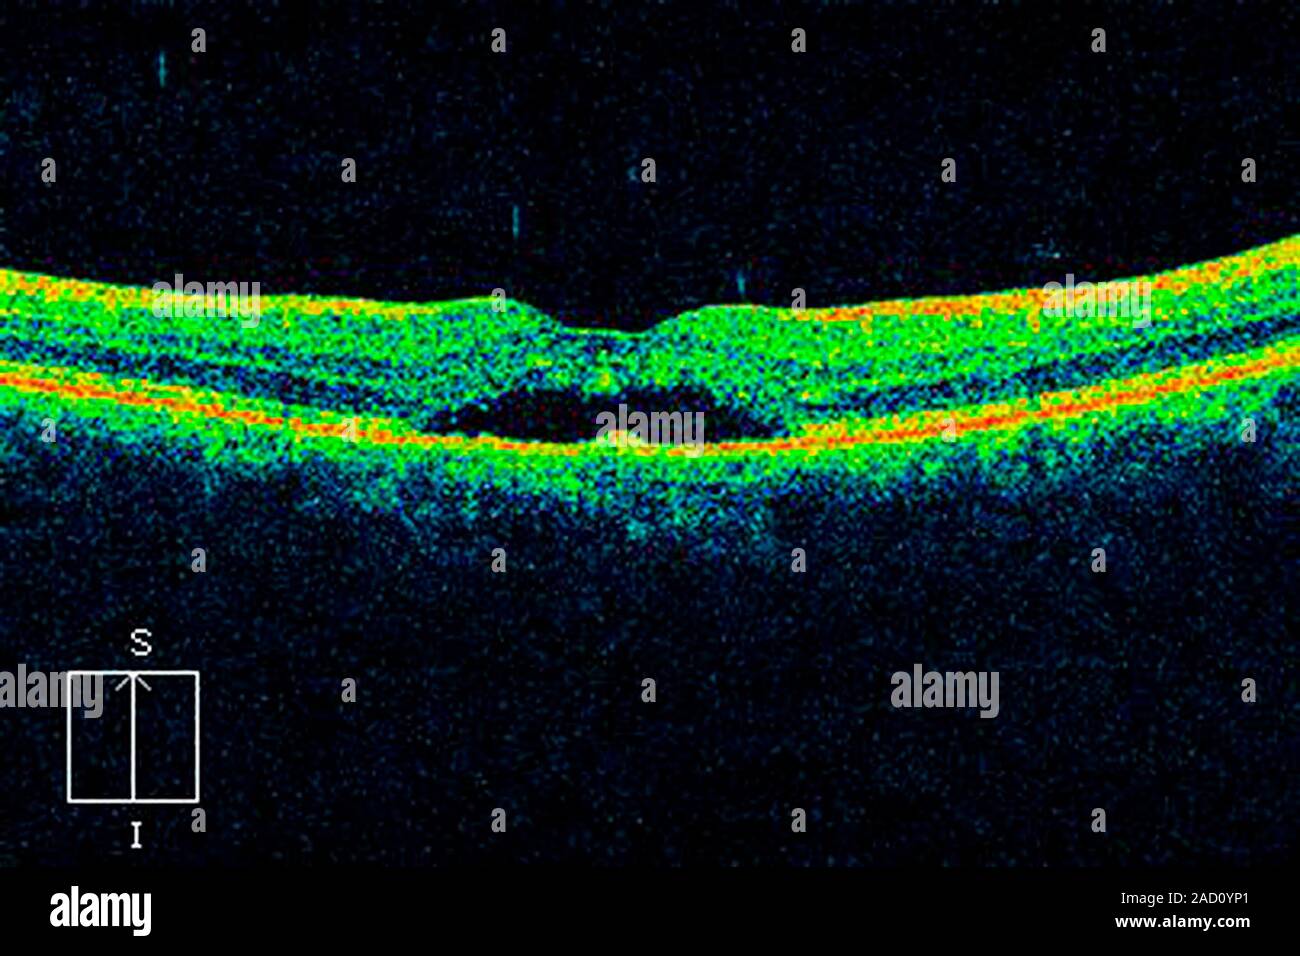

Macular degeneration. Optical coherence tomography (OCT) scan of a Macular Degeneration Oct Scan Oct is an imaging scan that uses light waves to take detailed images of the eye. Oct provides important information on serous retinal detachments, hemorrhages and subretinal neovascular membranes that are components of exudative macular. Read about the procedure, how oct scans work, and tips for. Optical coherence tomography is a quick, non invasive and reproducible imaging. Color photography shows. Macular Degeneration Oct Scan.